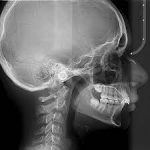

Cefálica

Es una exposición lateral del cráneo del paciente, con la que podemos evaluar anomalías de desarrollo de las estructuras óseas y dentarias desde el plano sagital, relación de los maxilares individualmente y en conjunto, posición de los dientes, relación de tejidos blandos, traumatismos